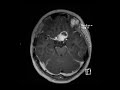

Optic nerve glioma

These images show a 2 cm lobulated T1 hypointense, T2 FLAIR hyperintense mass in the suprasellar cistern with cystic and enhancing solid components. There is mild mass effect on the superior aspect of the pituitary and the infundibulum is displaced to the left. The optic chiasm is obliterated by the mass and there is enlargement of the prechiasmatic left optic nerve. This turned out to be optic nerve glioma in a patient with a history of NF-1. Without the optic nerve involvement in a young child, the differential considerations include craniopharyngioma or germ cell tumor.